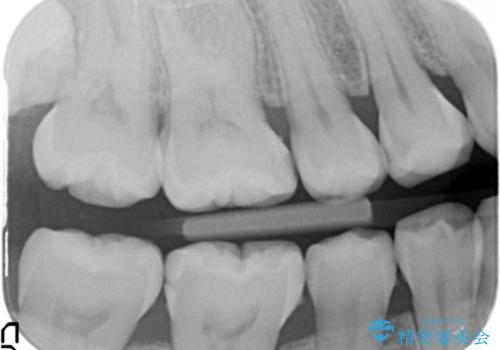

1. 奥歯の虫歯 セラミックインレーで治療の治療前